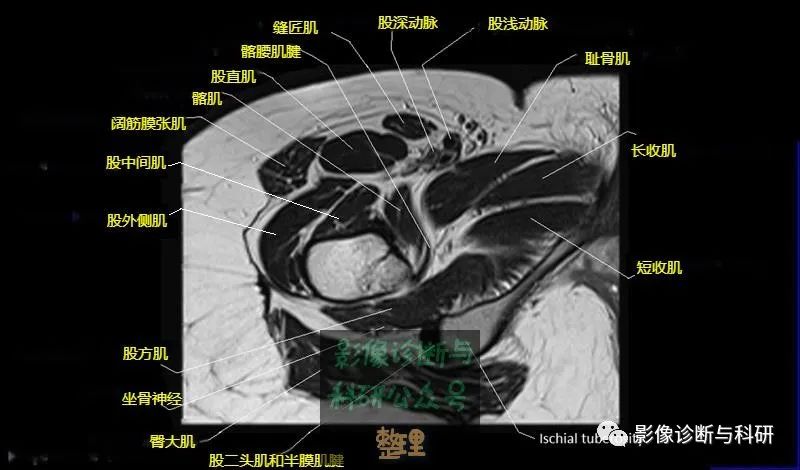

髋关节MR轴位详细标注

大腿肌配布于股骨周围,分前、后和内侧三群

前群

位于大腿前面,有缝匠肌和股四头肌。

内侧群

位于大腿内侧,共5块,其中股薄肌位于最内侧;另4块分三层,浅层靠外上方为为耻骨肌,下方为肌长收肌。长收肌深面是第二层的肌短收肌。第三层是强有力的大收肌。这一群肌均起自耻骨支和坐骨支,除股薄肌止于胫骨上端内侧外,其余各肌都抵止在股骨粗线。

后群

位于股骨后方,包括股二头肌、半腱肌和半膜肌。